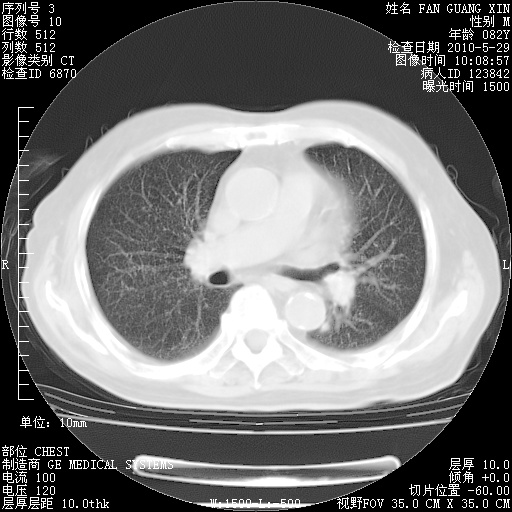

还需要哪些辅助检查?我们医院排除真菌感染没有任何检验方法,胸片好像能够排除肺部真菌感染。

补充:ENA化验全部阴性。免疫五项(IgG、IgA、IgM、C3、C4)只有C4略高。

CD3+ T细胞/淋巴细胞 46% (参考值50.00~84.00%)

CD3+CD4+ T细胞/淋巴细胞 21% (参考值27.00~51.00%)

CD3+CD8+ T细胞/淋巴细胞 25% (参考值15.00~44.00%)

CD3+CD4+ T细胞/CD3+CD8+ T细胞 0.84 (参考值0.71~2.78)

T细胞亚群是治疗5天采血。